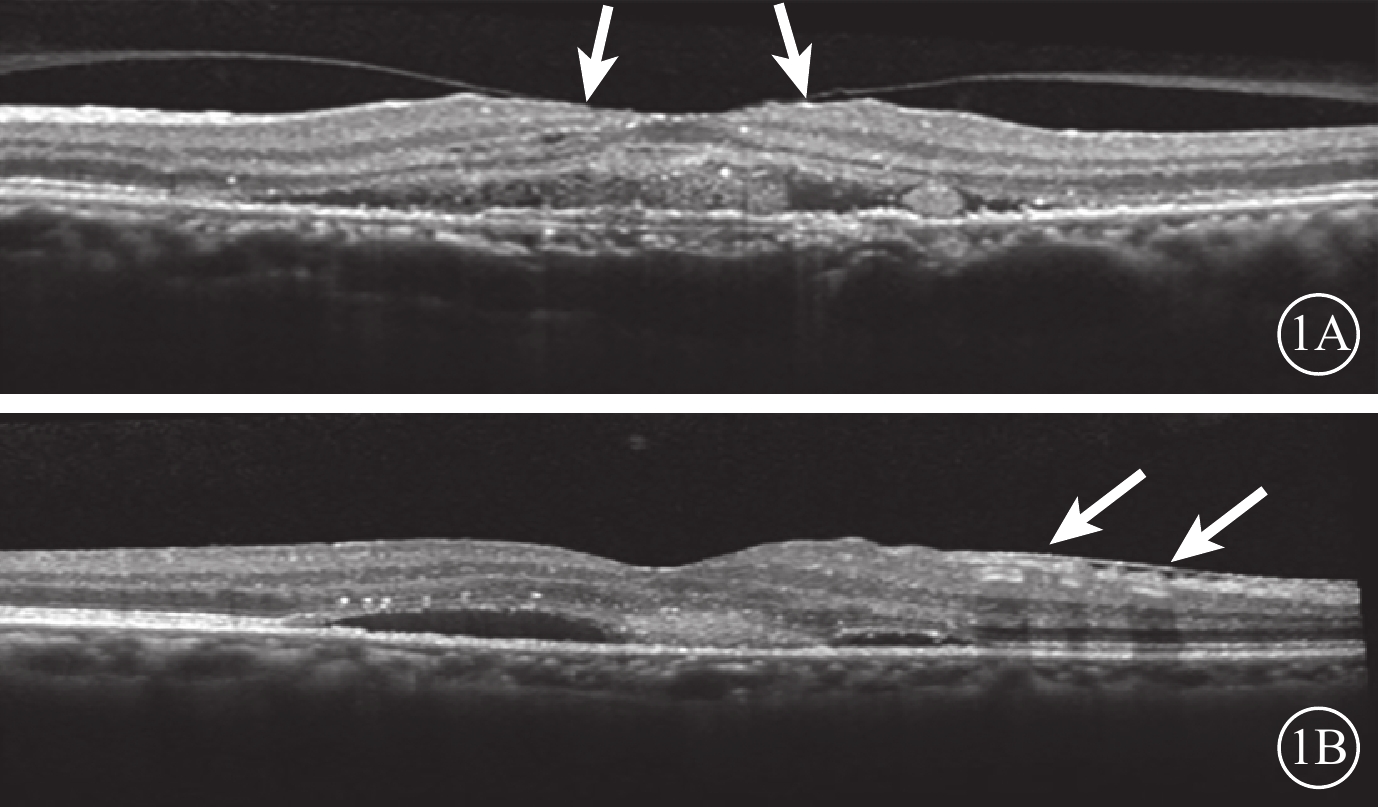

末次隨訪時,34只研究眼中,VMI異常12只眼。其中,廣泛型VMA 5只眼,局灶型VMA 2只眼,C-PVD 3只眼,MEM 2只眼;合并存在C-PVD、MEM 1只眼。與治療前比較,共有6只眼VMI發生變化(圖3)。34只對照眼中,VMI異常13只眼。其中,廣泛型VMA 5只眼,C-PVD 7只眼,MEM 1只眼。與治療前比較,共有6只眼VMI發生變化(圖4)。治療前研究眼中局灶型VMA 3只眼,其末次隨訪時發生C-PVD 2只眼。治療前對照眼中局灶型VMA 2只眼,末次隨訪時均發生C-PVD(表1)。